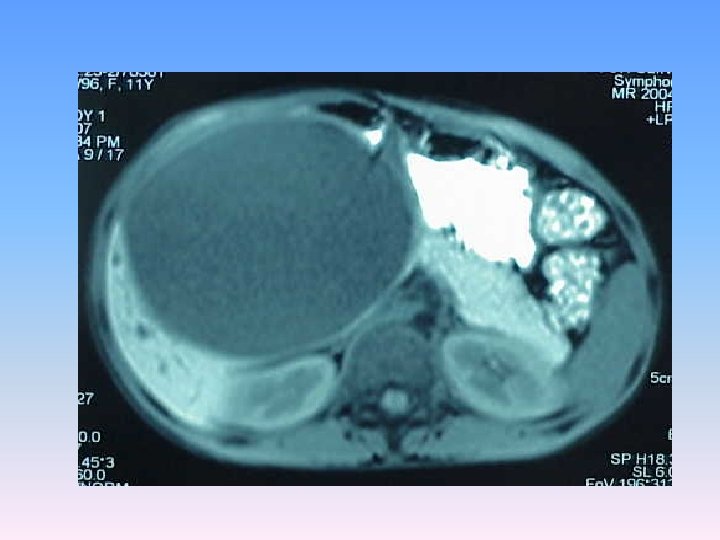

Abdominal CT Scan § A regular lobulated cystic mass in right lobe of liver (120 x 120) without calcification causing dilatation of intra & extra biliary ducts.

MRCP & MRI § Huge thicked wall cystic mass (140 x 120 mm), at the portahepatis that seems connected to biliary tree and gall bladder, resulted in severe dilatation of intra hepatic bile ducts and displaced right kidney posteriorly. § Spleen, kidneys, bowel loops and abdominal wall are normal. § Finding could be due to congenital anomalies like choledocal cyst, Duplication cyst, mesenteric cyst and hydatid cyst are in DDx.